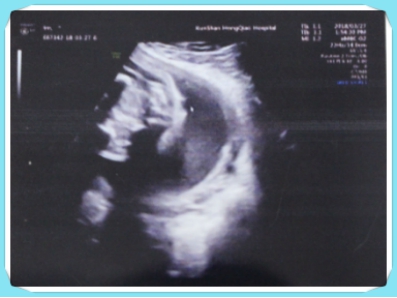

院正规不正规:四维彩超火眼金睛又查出畸形胎儿

397x298 - 67KB - JPEG